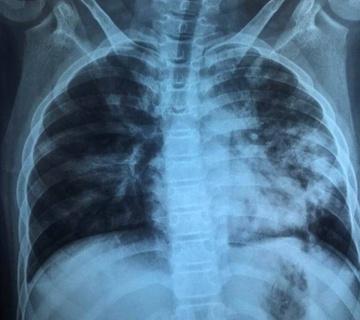

Dù triệu chứng bệnh không quá rầm rộ, kết quả X-quang khiến các y bác sĩ bất ngờ bởi phổi bé bị tổn thương nặng. Ngoài ra, các kết quả xét nghiệm cho thấy phản ứng viêm tăng cao, rối loạn đông máu.

Hình ảnh X-quang của bé lúc nhập viện, phổi tổn thương nặng. Ảnh: BSCC.